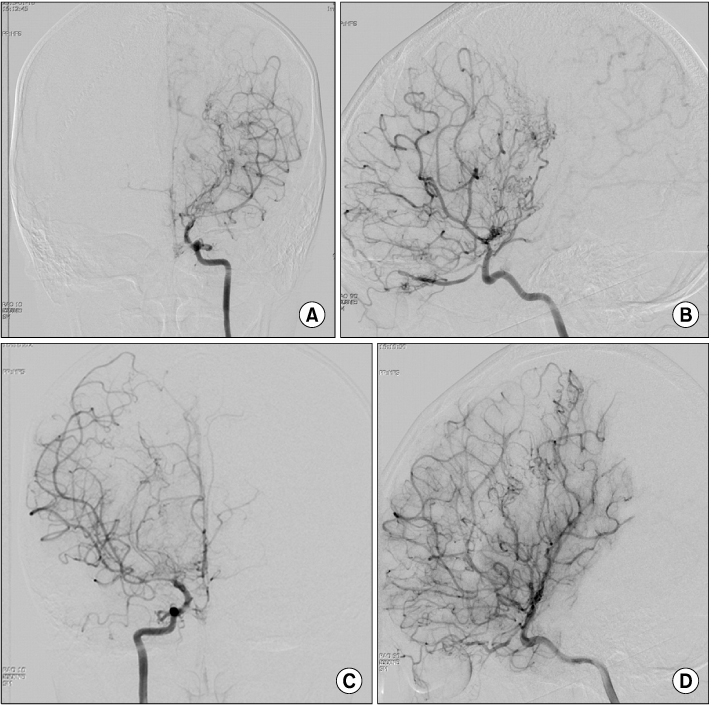

Fig. 1

A left carotid angiography (A, anteroposterior view; B, lateral view) shows severe stenosis in terminal portion of internal carotid artery and proximal middle cerebral artery and occlusion of proximal portion of anterior cerebral artery and demonstrates basal collateral vessels. A right carotid angiography (C, anteroposterior view; D, lateral view) demonstrates stenosis of proximal middle cerebral artery and occlusion in proximal portion of anterior cerebral artery.

Fig. 1 A left carotid angiography (A, anteroposterior view; B, lateral view) shows severe stenosis in terminal portion of internal carotid artery and proximal middle cerebral artery and occlusion of proximal portion of anterior cerebral artery and demonstrates basal collateral vessels. A right carotid angiography (C, anteroposterior view; D, lateral view) demonstrates stenosis of proximal middle cerebral artery and occlusion in proximal portion of anterior cerebral artery.